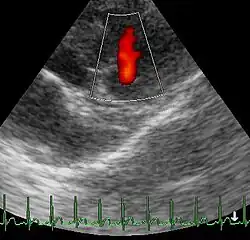

Üblich ist die Einteilung der Pulmonalklappeninsuffizienz in vier Schweregrade (Stadium I° bis IV°) in Abhängigkeit von der Blutdruckamplitude (= Pulsdruck = Pulsamplitude) bei der Rechtsherzkatheterisierung, vom Lagetyp im Elektrokardiogramm (EKG), von der Ventrikelkonfiguration im Röntgen-Thorax, von der Ventrikelgröße bei der Echokardiographie, vom Insuffizienzjet bei der Farbdoppler-Untersuchung und vom Blutrückstromvolumen bei der Herzkatheteruntersuchung. Bei dieser Einteilung wird eine Proportionalität zwischen den pathologischen Befunden und der Belastungseinschränkung unterstellt. Ein weiteres Maß für die Schwere der Insuffizienz ist die Klappenöffnungsfläche (abgekürzt KÖF).

Die Geschwindigkeit des zurückfließenden Blutes ist abhängig vom Druckunterschied zwischen Lungenschlagader und rechter Herzkammer. Sie wird echokardiographisch gemessen und kann anhand der Bernoulli-Gleichung zur Abschätzung des Drucks in der Lungenschlagader verwandt werden.[34]

Im Röntgenbild des Thorax oder im Kardio-MRT (Kernspintomographie) sieht man einen vergrößerten rechten Ventrikel und dilatierte Pulmonalarterien. Mit Hilfe der Farbdopplerechokardiographie und auch der Computer-Tomographie kann das Ausmaß der Insuffizienz beurteilt werden.[35] Die Diagnose wird nach einer Herzkatheterisierung und nach einer Angiokardiographie gestellt.[36]